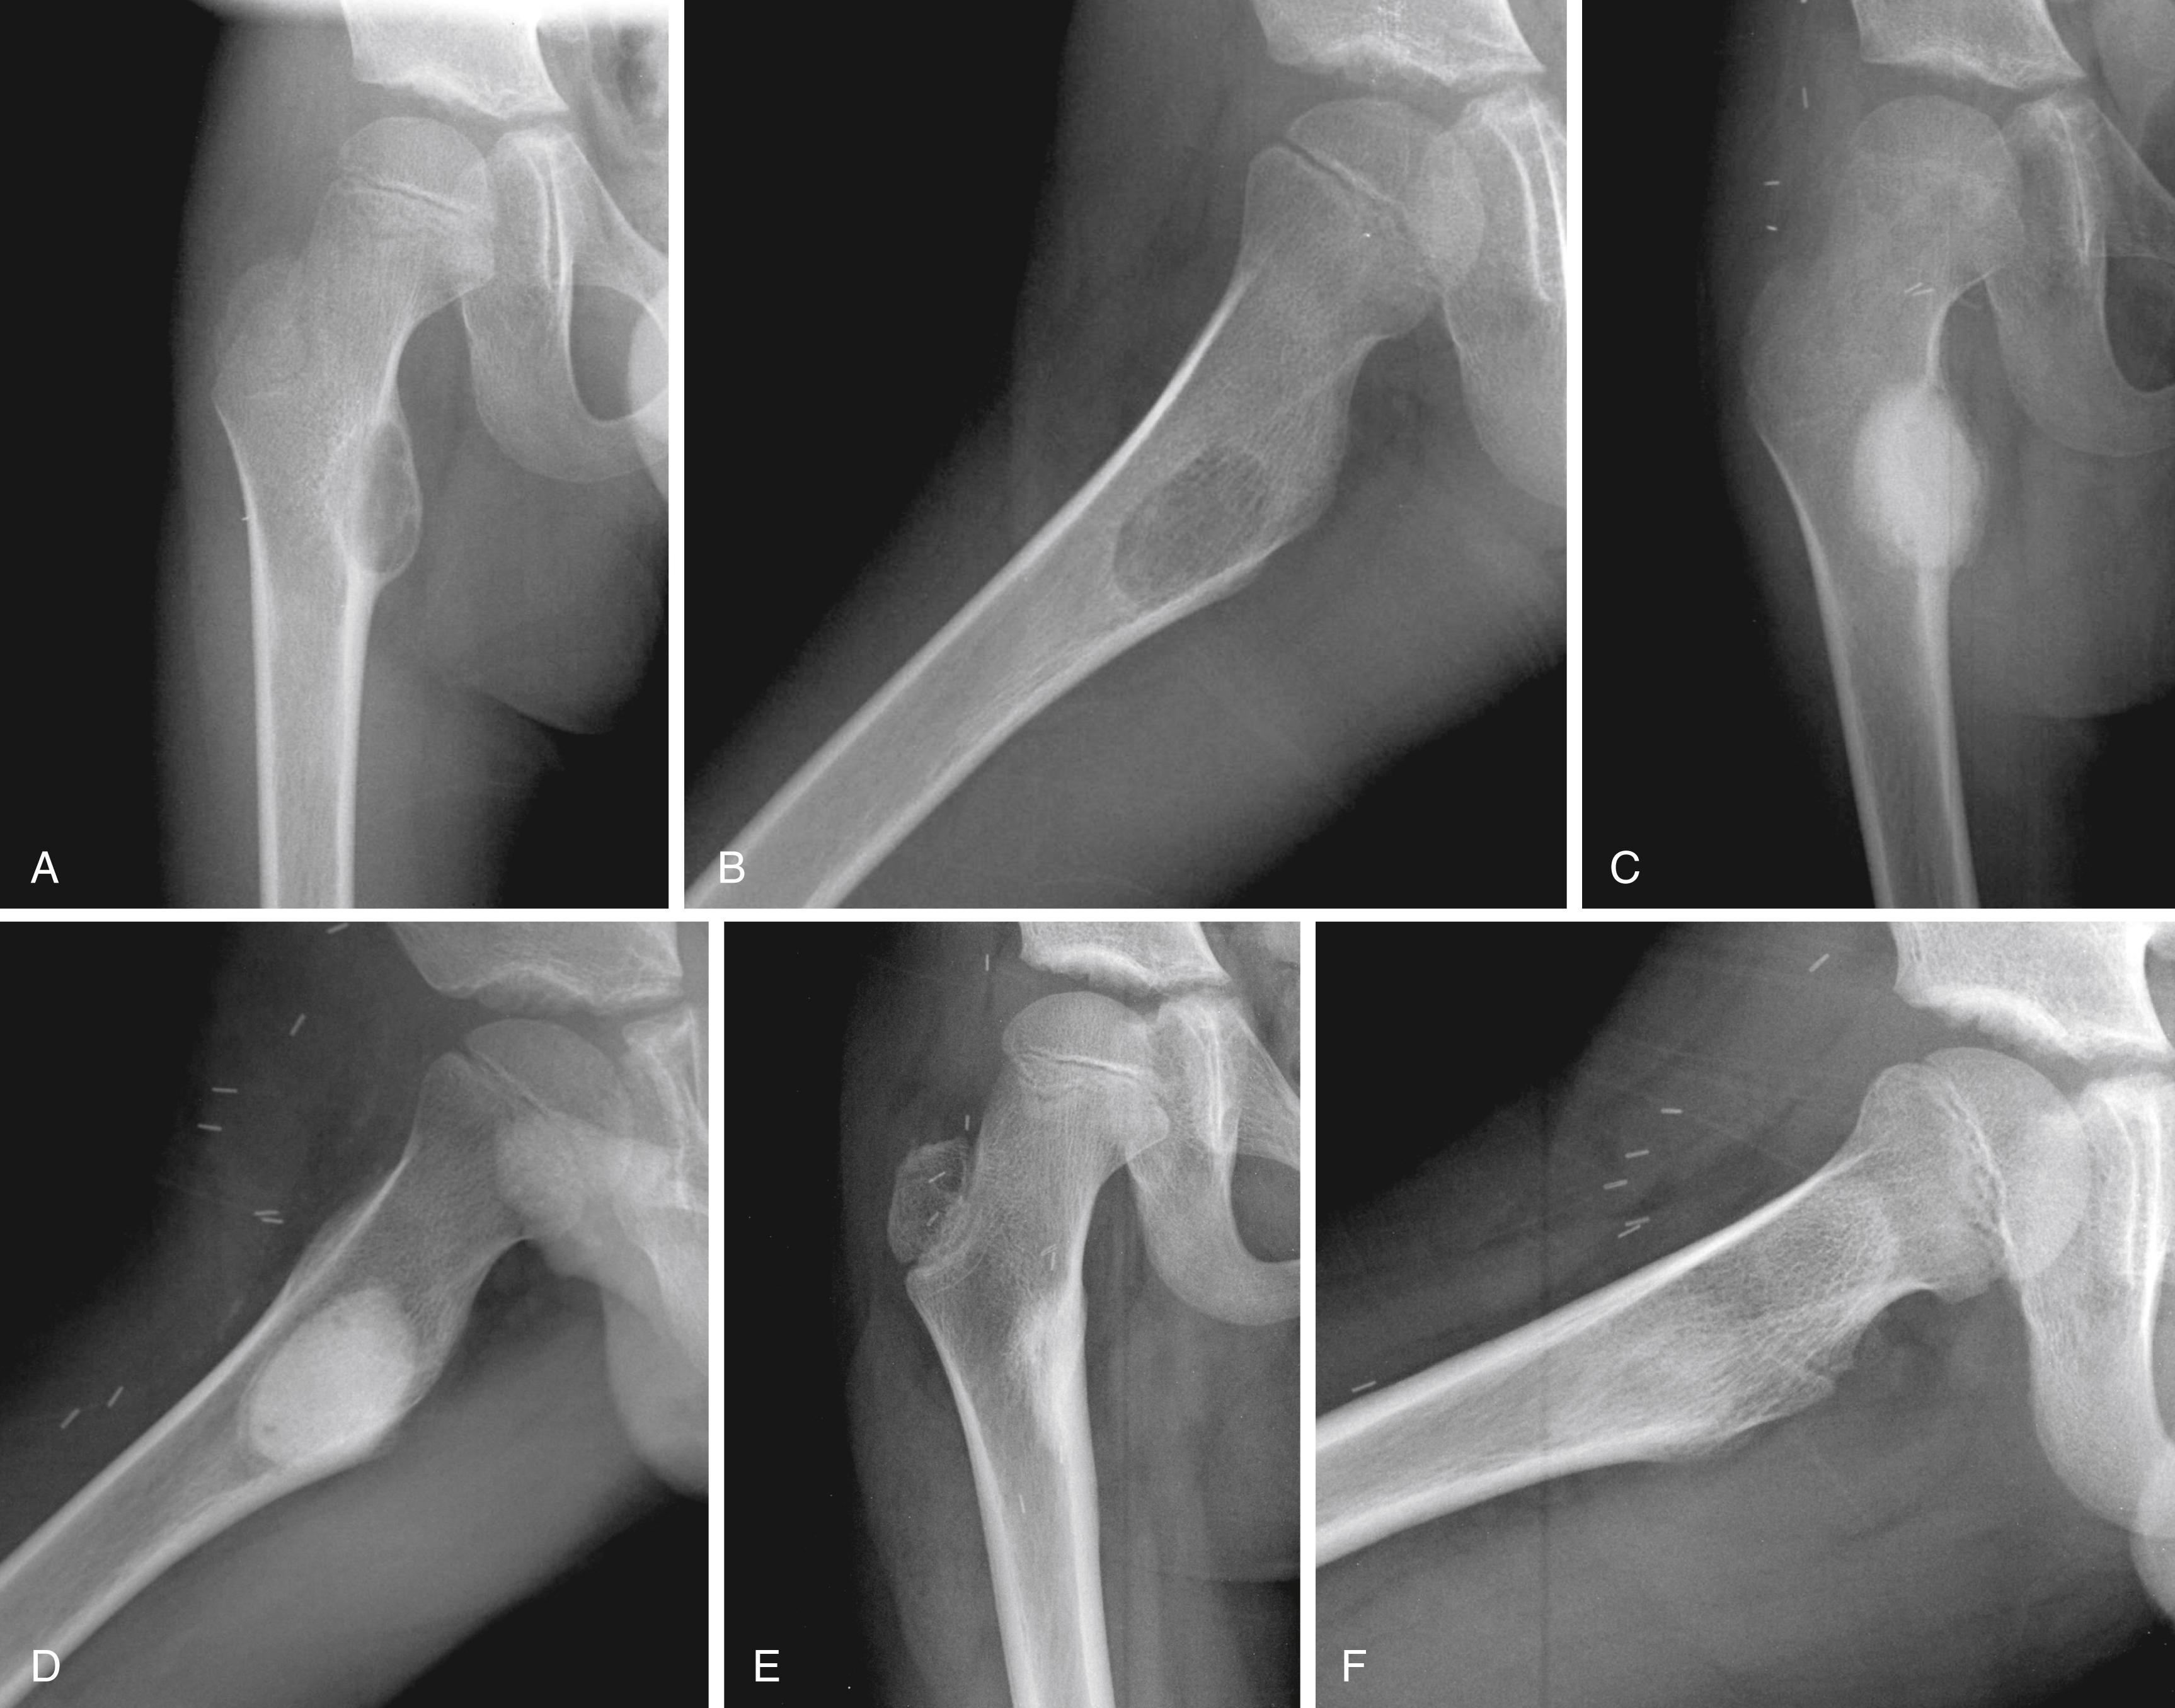

Radiographic findings usually are characteristic. This well-circumscribed lesion is usually centered in an epiphysis of a long bone; however, it may also be located in an apophysis, such as the greater tuberosity ( Fig. 26.6 ) or the greater trochanter ( Fig. 26.7 ). Often it has a surrounding rim of reactive bone ( Fig. 26.8 ), and 30% to 50% exhibit matrix calcification. CT can be helpful in detecting subtle areas of calcification that may or may not be detectable on plain radiographs. MRI frequently demonstrates abundant surrounding edema. Soft-tissue extension is extremely rare. In children, a well-circumscribed epiphyseal lesion that crosses an open physis is highly suggestive of chondroblastoma but could also represent an infectious process. For adults, differential diagnoses for an epiphyseal lesion include giant cell tumor and clear cell chondrosarcoma. In contrast to chondroblastomas, however, giant cell tumors usually do not have a rim of sclerotic bone or intralesional calcification and may have a soft-tissue component.

FIGURE 26.6, Chondroblastoma in a 16-year-old boy.

FIGURE 26.7, Chondroblastoma in a 12-year-old boy.

FIGURE 26.8, A and B, Anteroposterior radiograph and CT scan of a 16-year-old girl with a chondroblastoma of the femoral head. The lesion is epiphyseal and has a narrow zone of transition with a thin rim of reactive bone and a small amount of matrix mineralization. C, MR image demonstrates the lesion with extensive surrounding edema and an effusion. D, Extended curettage was performed through an anterior approach followed by the placement of a bone graft substitute (E) .